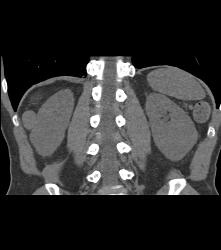

Diagnosis

Dense Renal Cyst